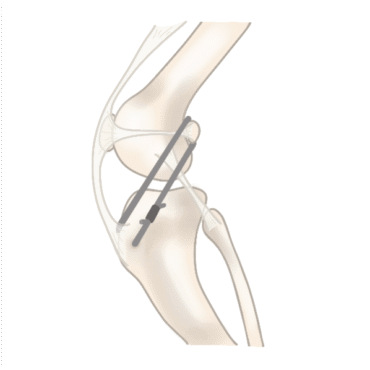

De kunstband (Flo-teugel)

Voor kleinere honden, lichter dan 15 kg, passen we vaak de zogenaamde kunstbandtechniek toe, ook wel de Flo-teugel genoemd. Hierbij wordt de functie van de gescheurde kruisband nagebootst met een stevige band die buiten het kniegewricht wordt geplaatst. Dit stabiliseert de knie zodat de hond zich weer goed kan bewegen. Deze techniek is niet geschikt voor grotere honden omdat de kunstband daar niet sterk genoeg voor is.

Schematische weergave van de Flo-teugel